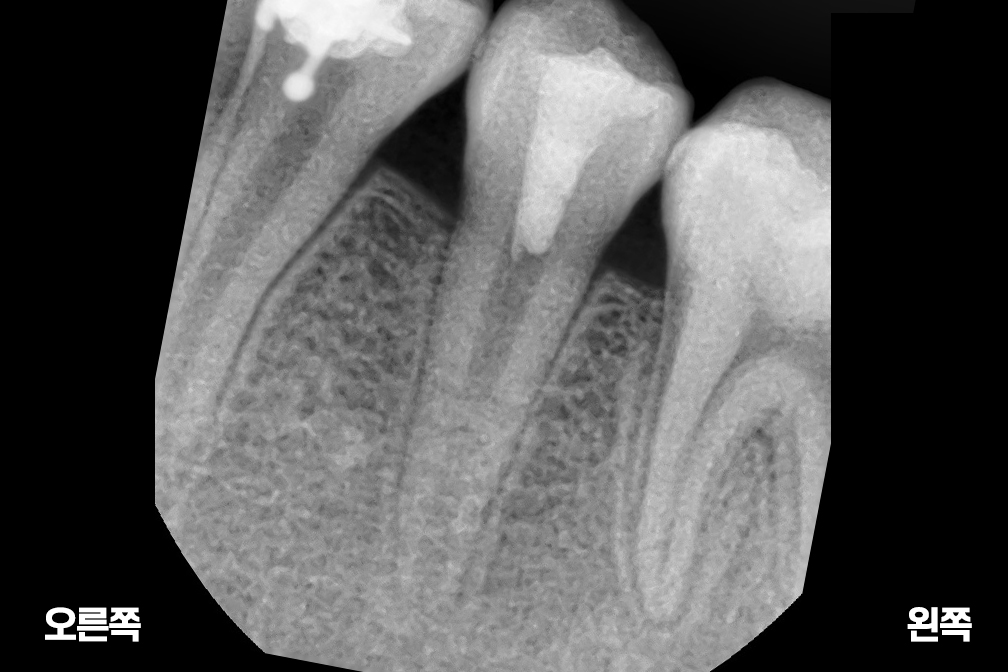

After 2025년 6월 25일